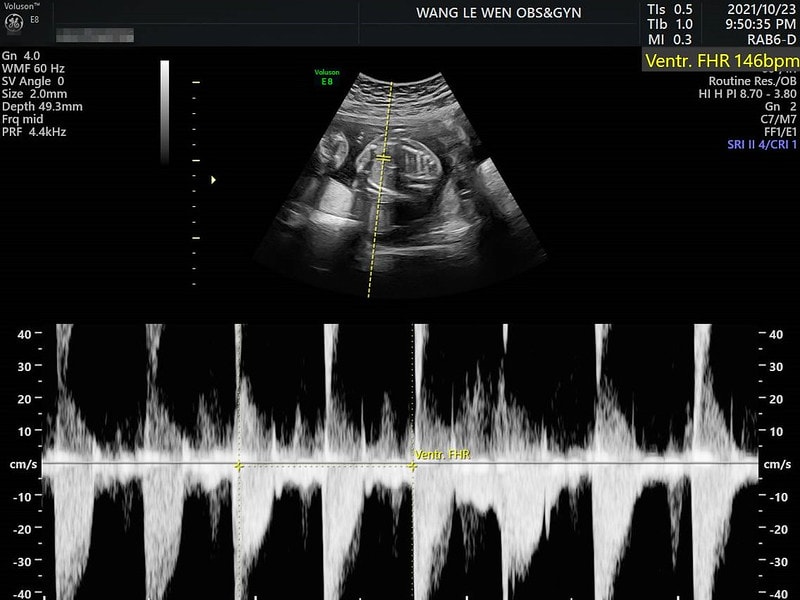

關於第一次聽到小孩的心跳

其實內心也是滿激動的

一直都覺得自己雖然這個年紀了

還是覺得很像小孩哈哈哈

所以對自己有小孩也是想滿多的

我本來就是挺多慮的類型